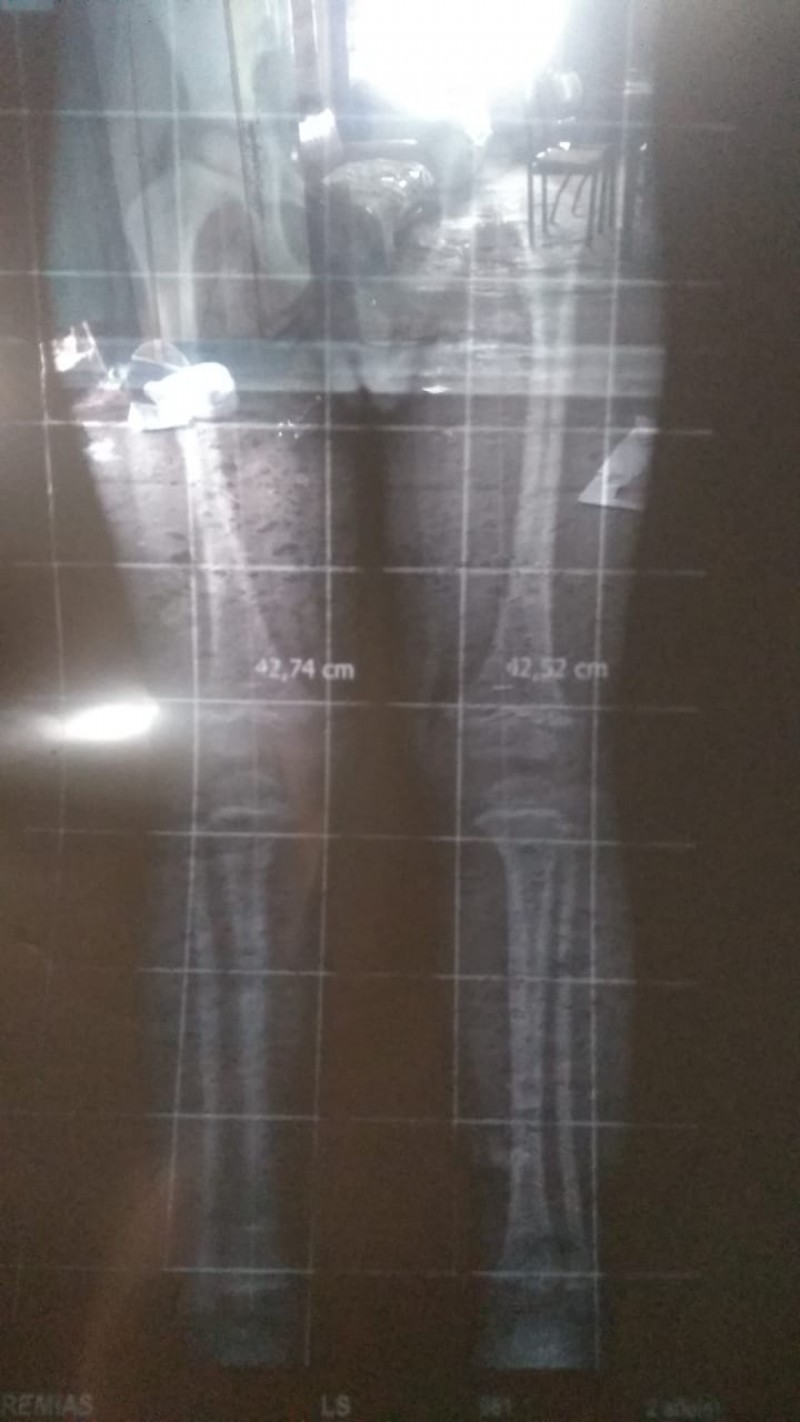

El informe médico.

En diálogo con este medio, Jesica explicó que Jeremías tiene 2 años y medio y, desde su nacimiento, padece de una descalcificación en los huesos, una desviación en la columna y una pierna más larga que la otra. De allí la necesidad de contar con las plantillas ortopédicas.